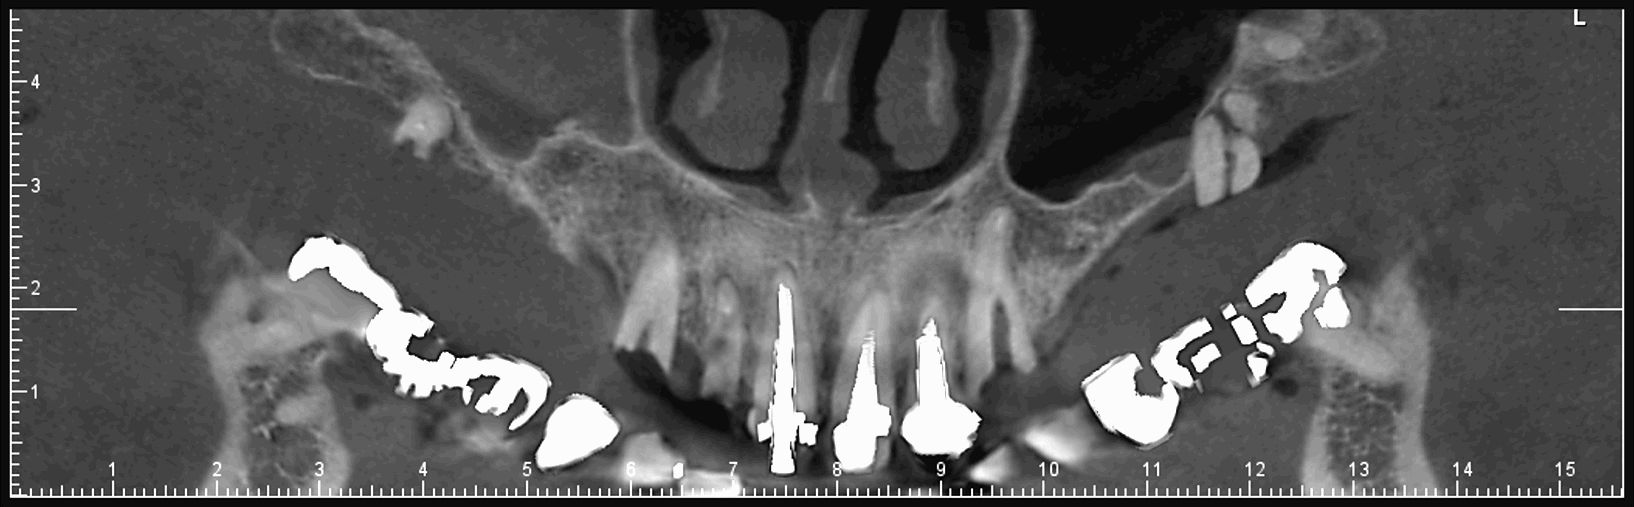

Les nouvelles générations de scanner permettent de faire une acquisition d’un volume global d’une partie du corps et de travailler à l’intérieur de ce volume en isolant une structure anatomique donnée et de l’explorer dans tous les plans de l’espace.

Grace à la technique de seuillage il est possible de dissocier progressivement les dents des structures osseuses environnantes dans le volume donné.

- Pour le scanner, vous serez allongé sur une table qui se déplacera à l’intérieur d’un anneau. Vous devrez serrer entre vos dents un coton afin que les dents ne se chevauchent pas.